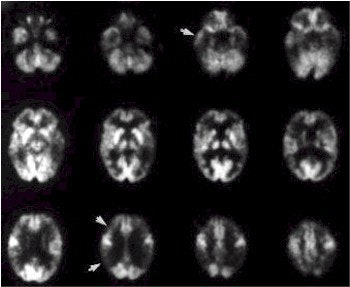

FDG-PET scan of woman, 54, with progressive dementing illness. Note significant reduction in FDG in parietal, temporal, and frontal cortices indicated by arrows. The metabolic pattern of this patient would be considered classic for AD (JNM, November 2000, Vol.41:11, p.1923).